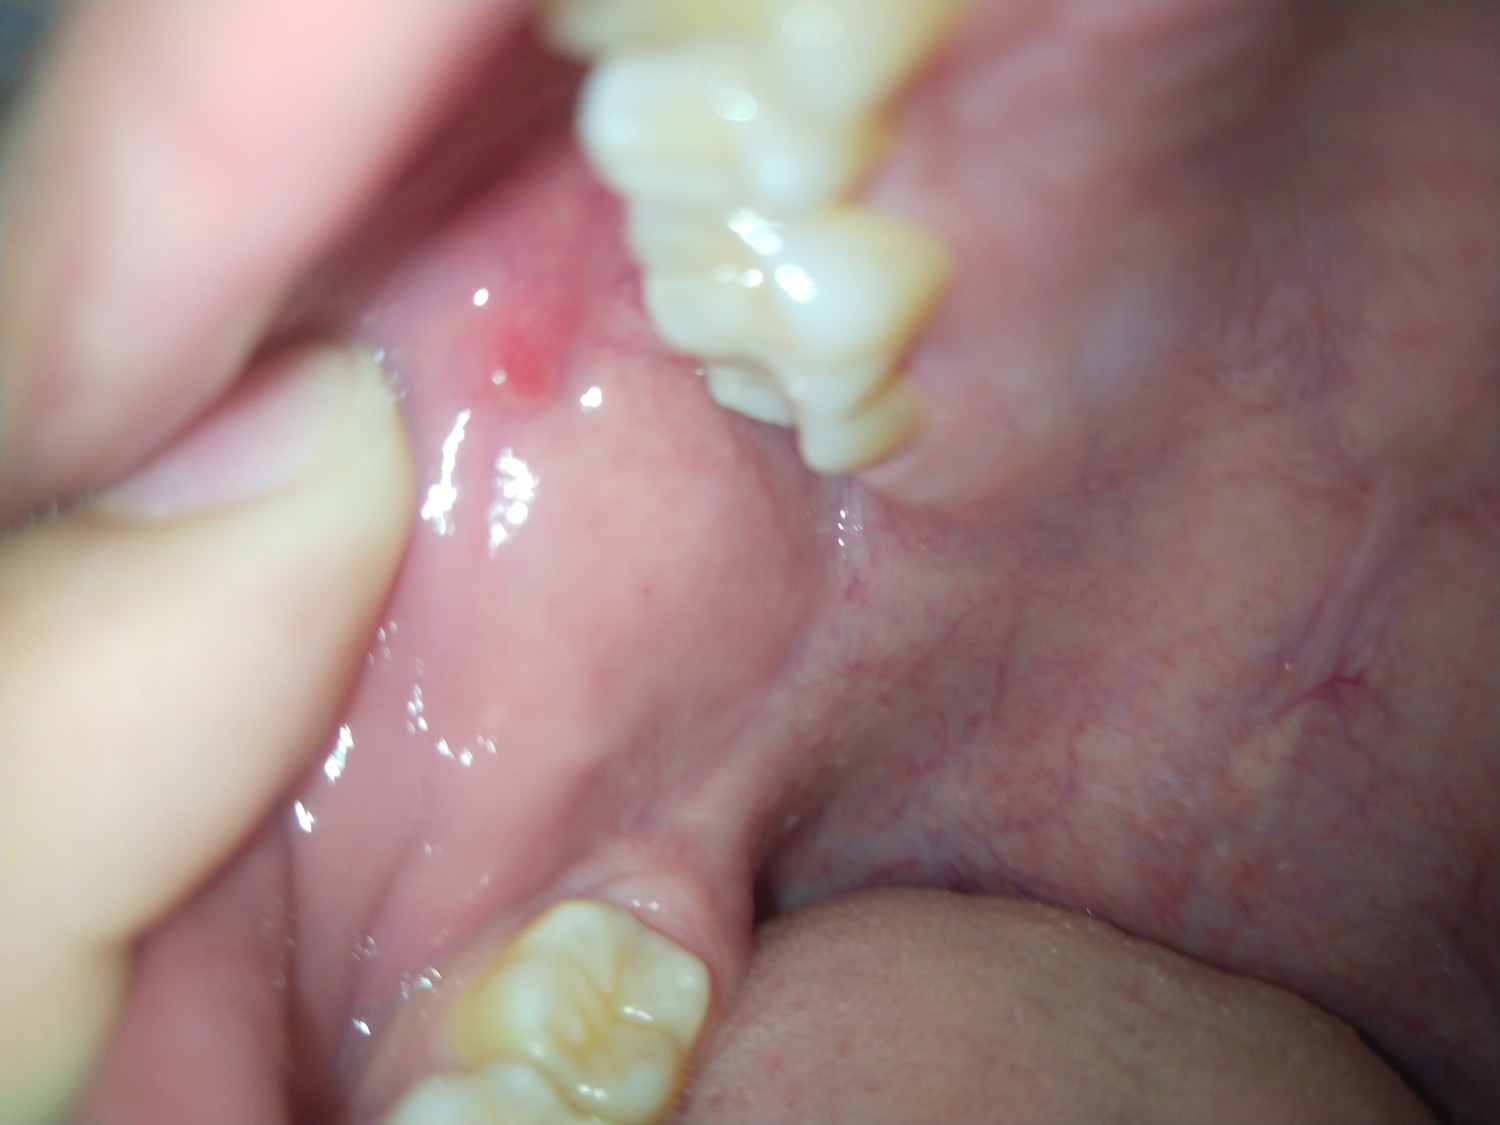

ติ่งเนื้อในปาก

เป็นติ่งแดงๆในปากแบบนี้คือไรครับ